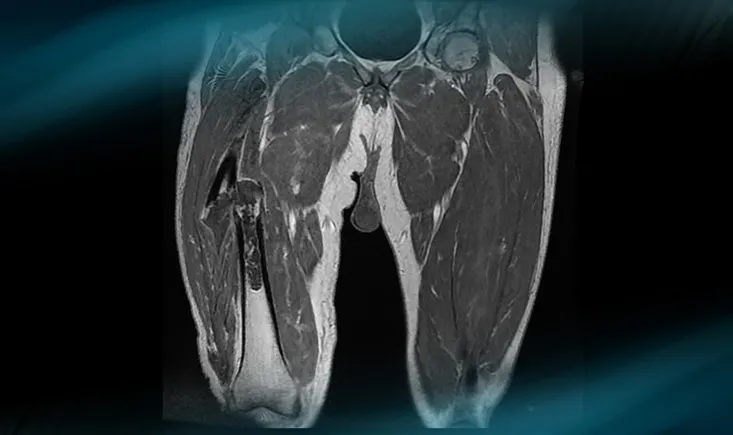

Frane Bukvić presents the case of a 34-year-old orthopaedic surgeon​ suffering from a symptomatic chondral ‘ki…